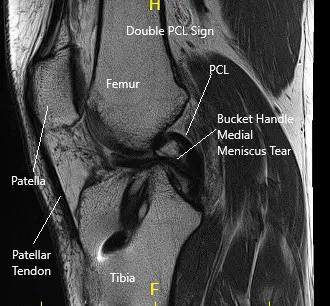

MRI of the right knee suggested a large bucket-handle tear of medial meniscus, displaced into the intercondylar notch and over the anterior horn.

MRI of the right knee in the sagittal and coronal section.